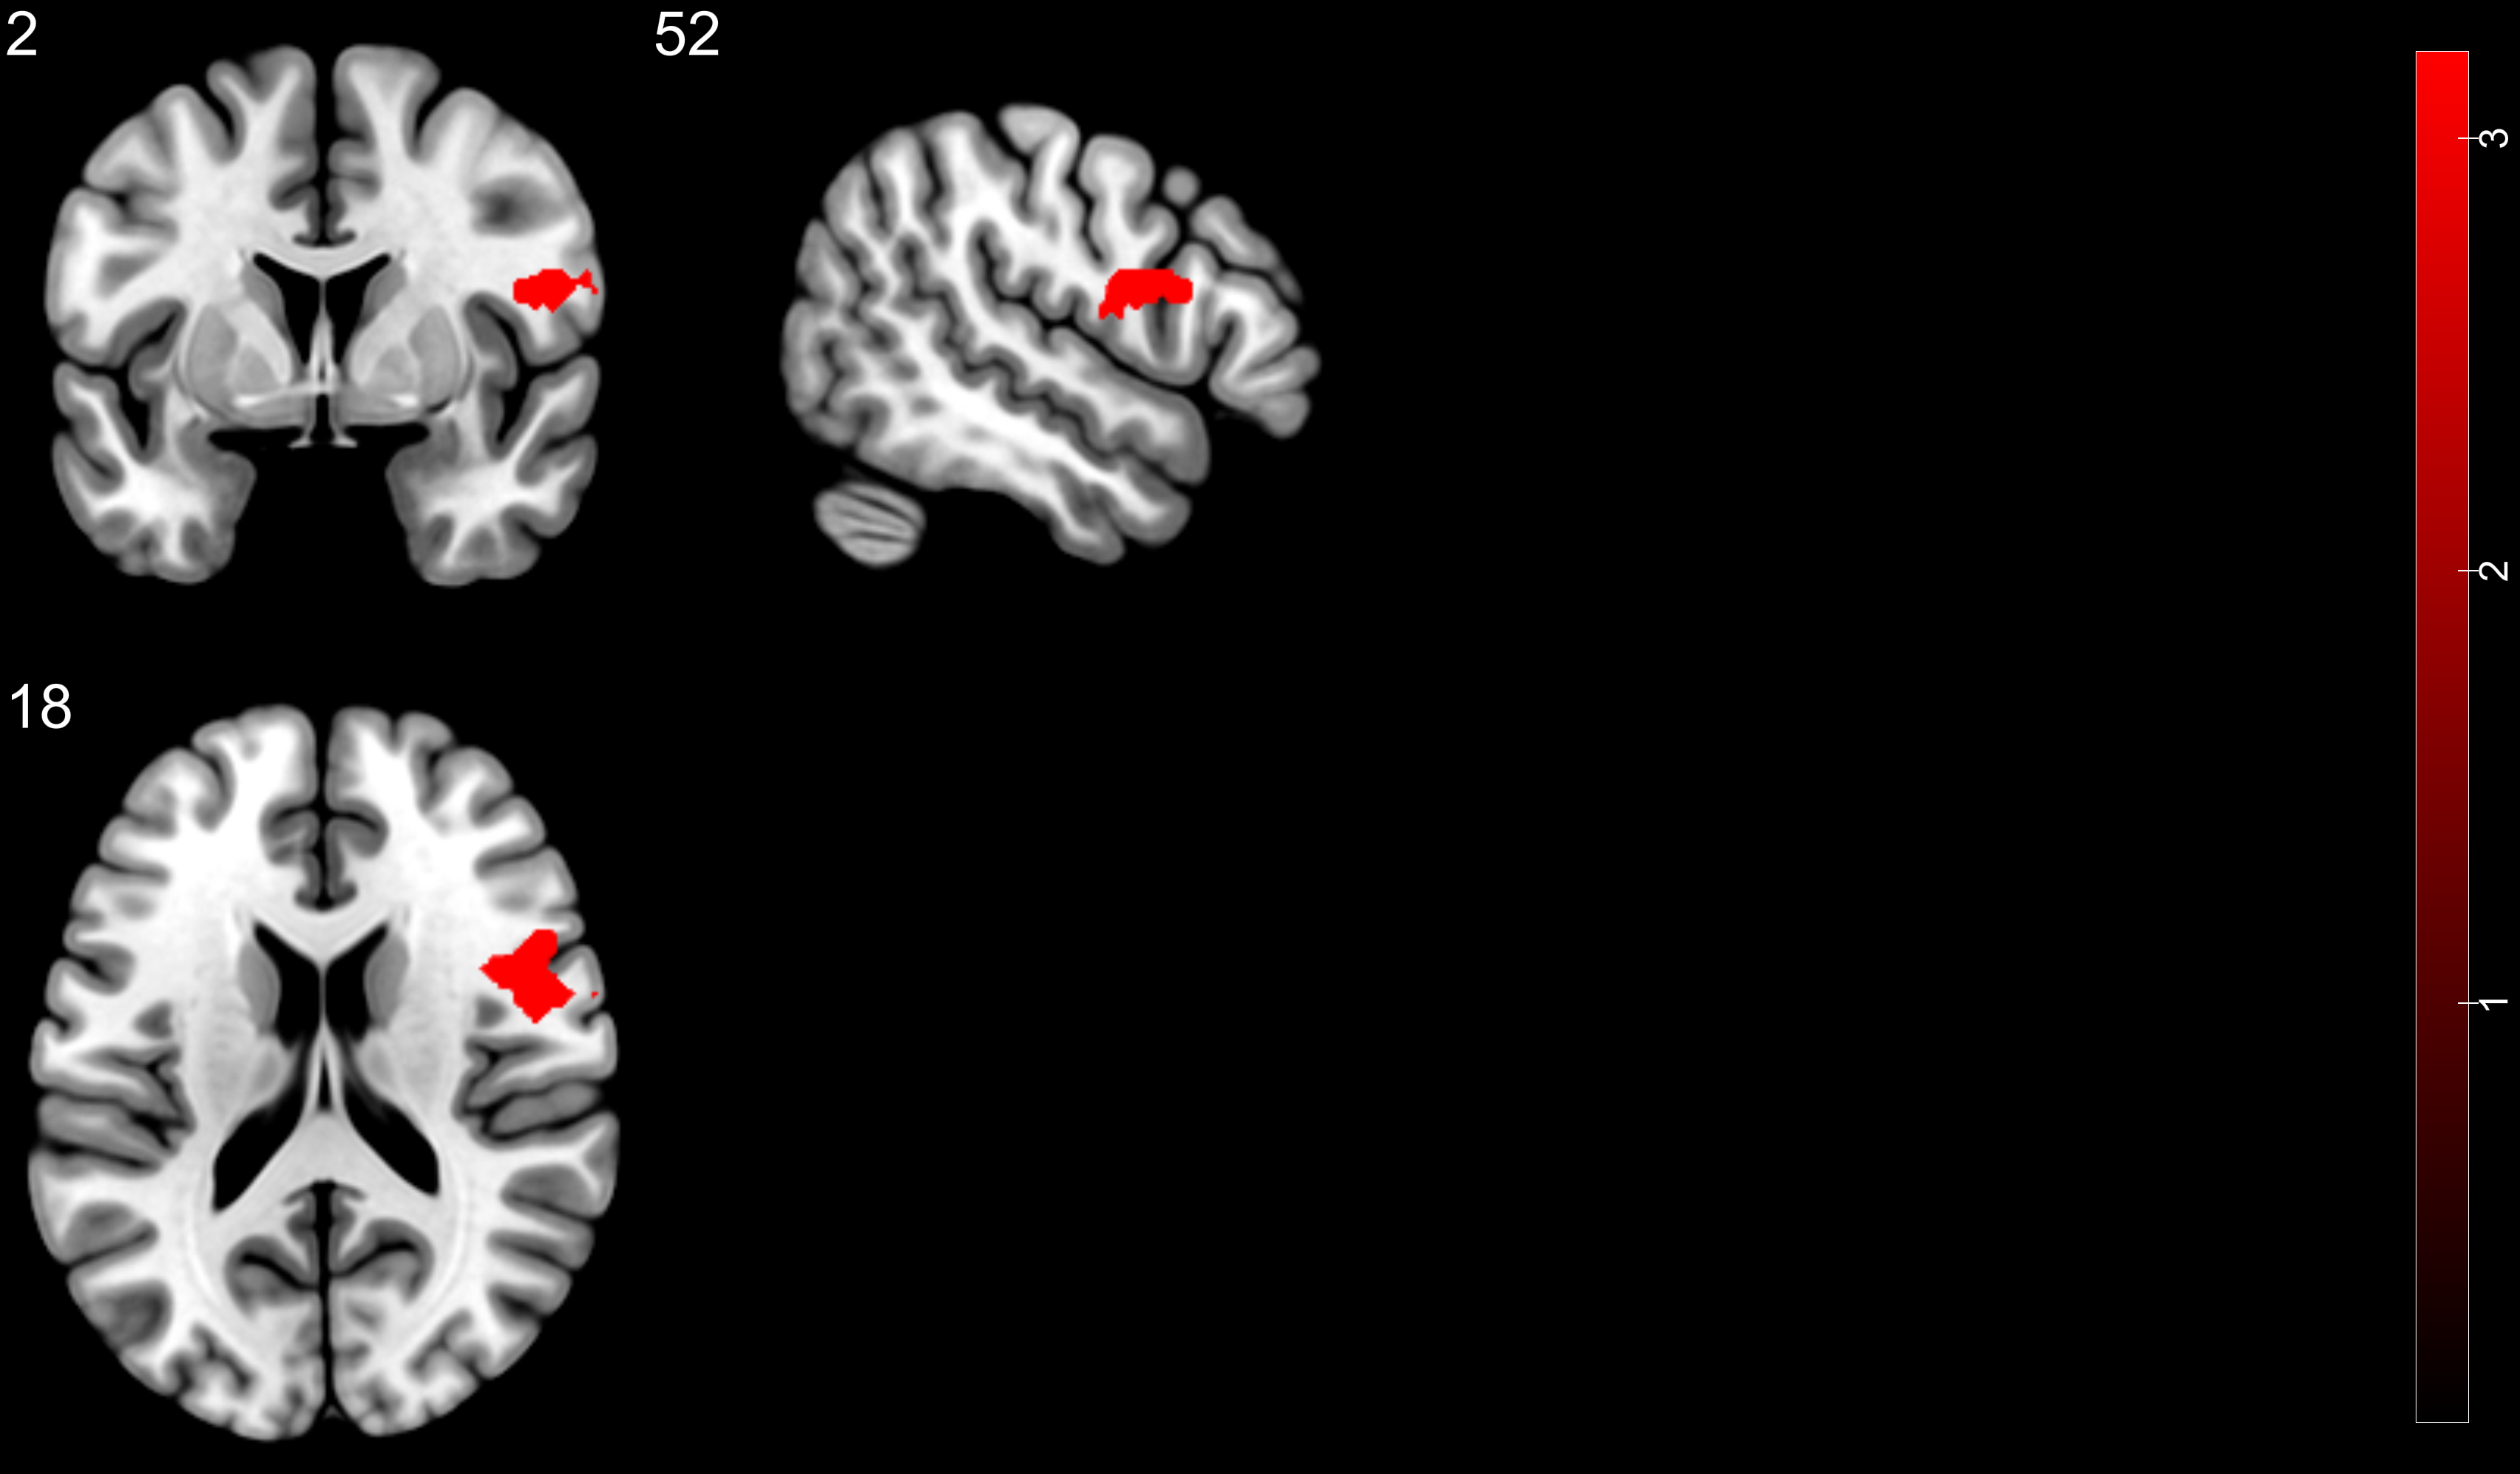

After exporting a mask from SPM and adding said mask as an overlay on in mricrogl, BOLD response shows no gradient, it is one solid color (please see attachment). How do I show gradient?